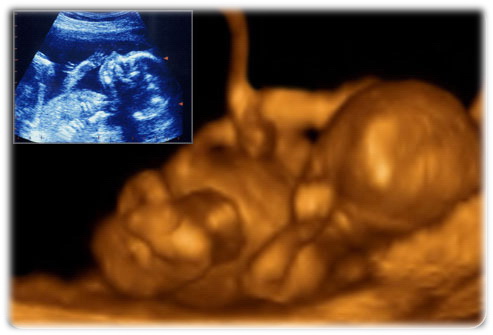

تأخذ صوره بالأشعه الفوق سمعيه (ultra-sound) للجنين عادة في الإسبوع العشرون. في هذا الفحص يتأكد الطبيب بأن الحبل السري مربوط بالجنين والأم بشكل سليم. يتمكن الطبيب أيضاً من رؤية حركة اليدين والقدمين وكذلك رؤية دقات القلب. في هذه المرحله من الممكن التعرف على جنس الجنين

صوره ثلاثية الأبعاد. بسبب إكتمال تتطور الأذنين عند هذه المرحله يعتقد العلماء بأن الطفل يمكنه معرفة إن كان مقلوباً رأساً على عقب في بطن أمه ! ونتذكر في هذا السياق قوله تعالى " قال فمن ربكما يا موسى ﴿٤٩﴾ قال ربنا الذي أعطى كل شيء خلقه ثم هدى ﴿٥٠﴾ " {سورة طه}